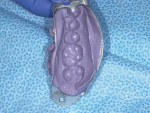

The basic procedure for producing a provisional crown is illustrated in Figure 1 through Figure 10. There are a number of provisional materials that are in widespread use today. This article will examine several provisional material products.

![Figure 2 Figure 2 The tray is filled with a matrix

impression material (Template® [Clinician’s Choice] shown here) to create the template for the provisional crown](/media/thumbnail/44605/150x150)